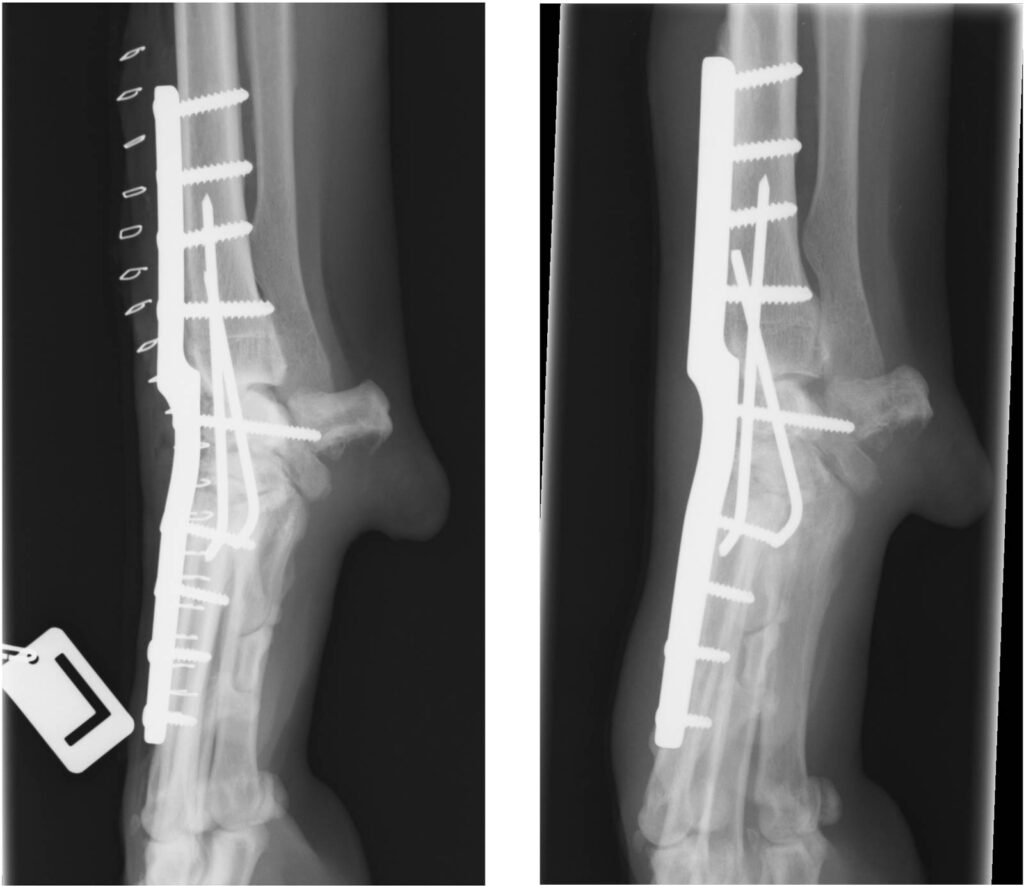

Injury or degeration of the palmar ligament can cause the carpus to ‘sink’. Failure of the palmar ligament can occur at one or more levels and it is important to assess the injury carefully. Splinting or casting of such injuries is destined to fail and surgery is receommended. However, careful assessment of the injury is required because if the antebrachiocarpal joint is unaffected, and can be saved, this has important long-term consequences for the dog. If this is the case, partial carpal arthrodesis can be performed using specially designed plates and bone graft.

If the antebrachiocarpal joint is affected, full fusion (pancarpal) arthrodesis can be performed and will restore function in the short-medium term although arthritis of neighbouring joints is likely in the long term. Careful assessment of these injuries with a specialist is recommended so that clients can make infiormed decisions for their pet.